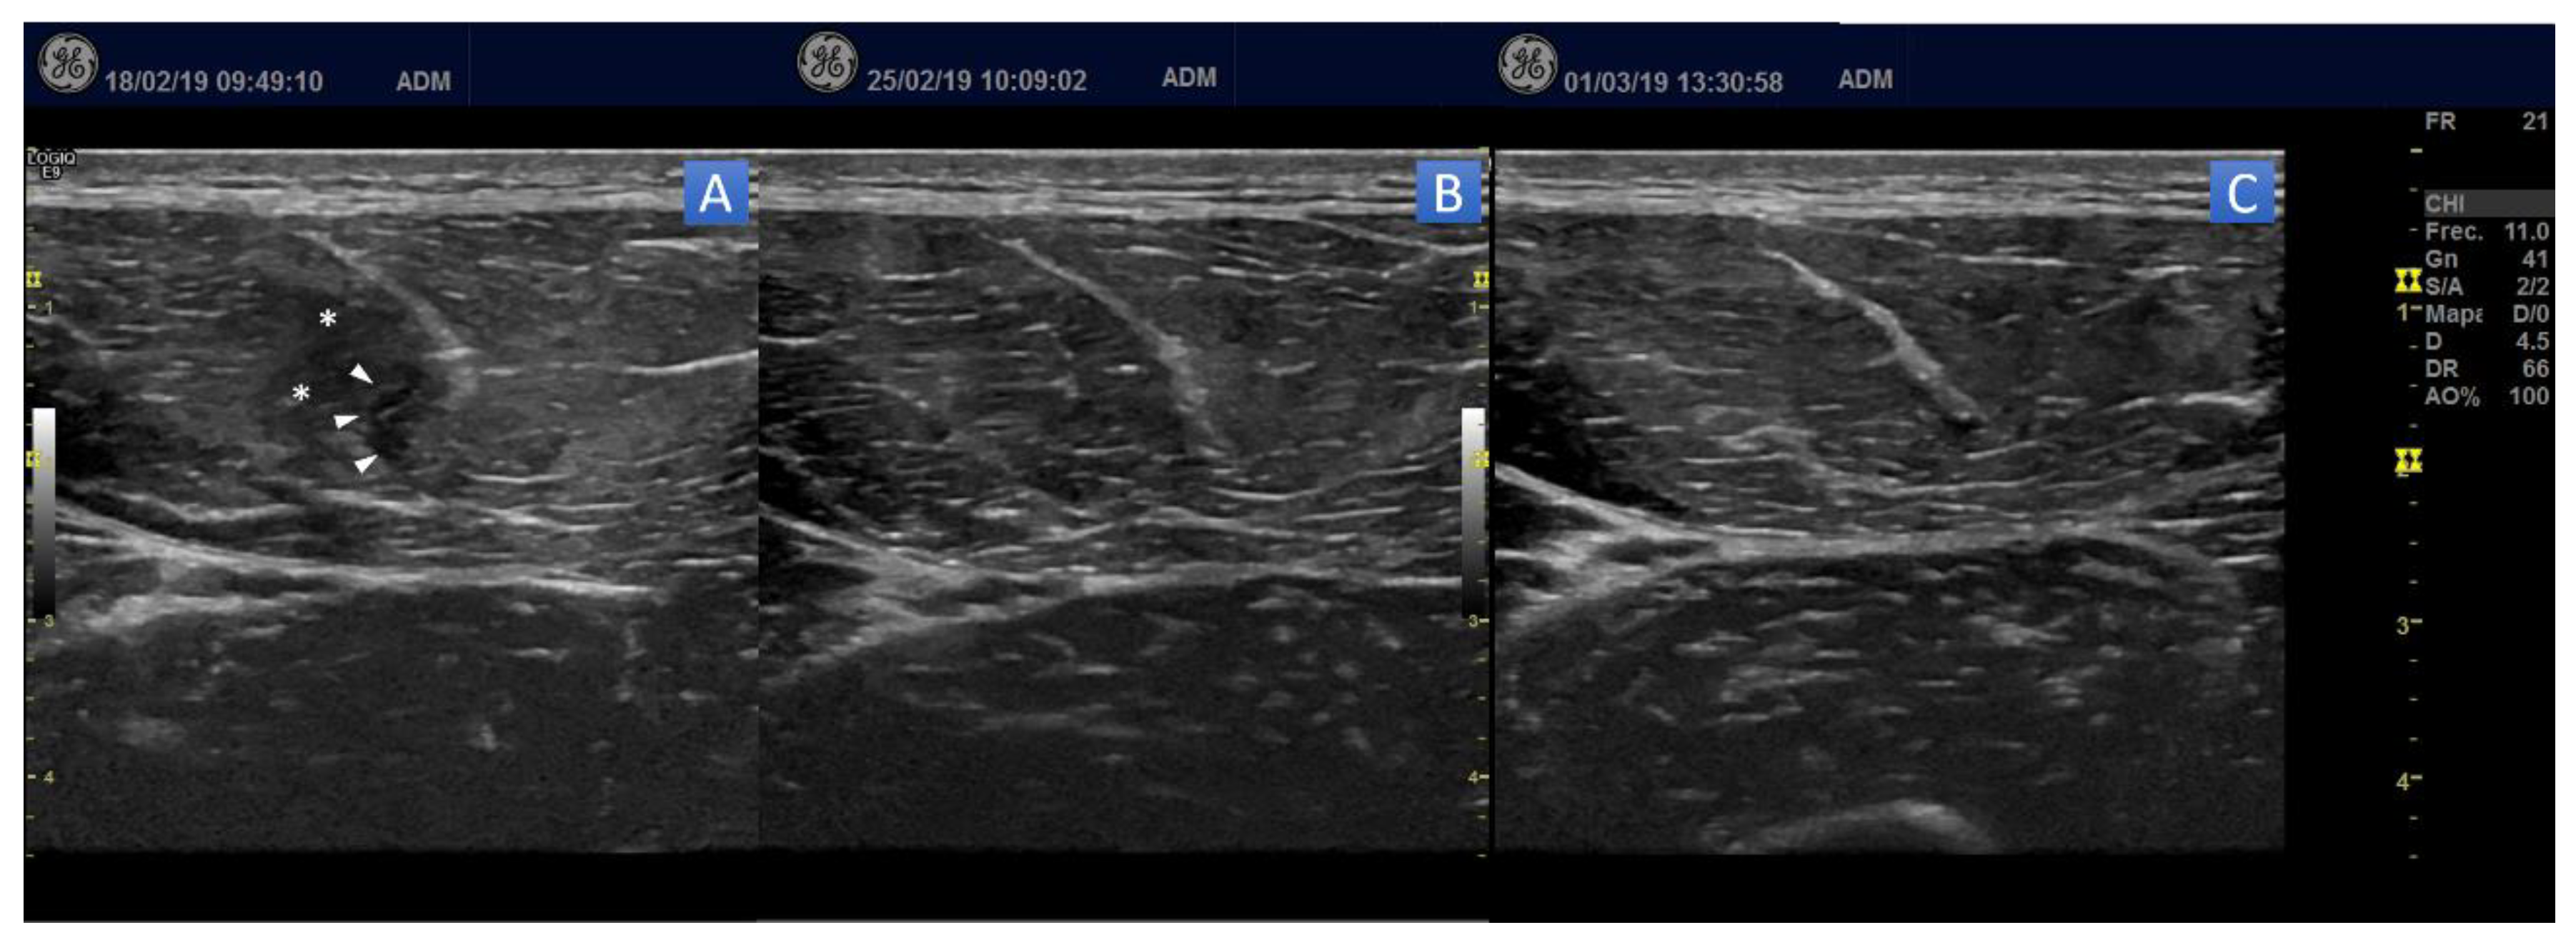

Initially, all players presented images showing a fibrillar defect in the myotendinous junction of rectus femoris muscle with surrounding edema, without fluid collection/hematoma drainable, consistent with a grade II strain injury (Figure 3A). In 92.3% of the cases, the ultrasound examination in the day 7 post-PNE showed a significant change in the extent of edema and fiber disruption (Figure 3B). One player needed one additional session of PNE (7 days post-PNE-1). Ultrasound follow-up at 14 days showed an almost complete disappearance of the injury pattern of the muscle in all players in the ultrasound image (Figure 3C).

Figure 3.

Transverse B-Mode ultrasound images of the evolution of the injured muscle. (A) Initial. 48 h post-injury. Ultrasound imaging shows muscle fiber discontinuity at the level of tear (arrowhead), with surrounding echogenic muscle edema (asterisk). (B) Ultrasound imaging at seven days post-PNE. (C) Ultrasound imaging at 14 days post-PNE.